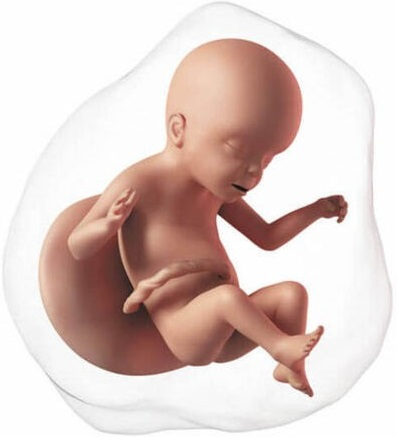

En esta semana inicia el segundo trimestre del embarazo. El feto mide aproximadamente 80 y 95 mm. El bebé crece rápidamente, los brazos alcanzan la proporción adecuada en relación al tamaño del cuerpo. La piel, que ya no es tan "transparente", se cubre aún más por vello denominado lanugo. Los músculos de la cara se desarrollan más, su sistema nervioso está más desarrollado, abre la boca en forma de bostezo, hasta se pueden meter los dedos en la boca. Al abrir la boca entra líquido amniótico, el cual pasa al estómago y los intestinos, lo cual permite que estos crezcan y se desarrollen.

Tu abdomen empieza a crecer, se pierde tu cintura y se produce un aumento progresivo de peso.